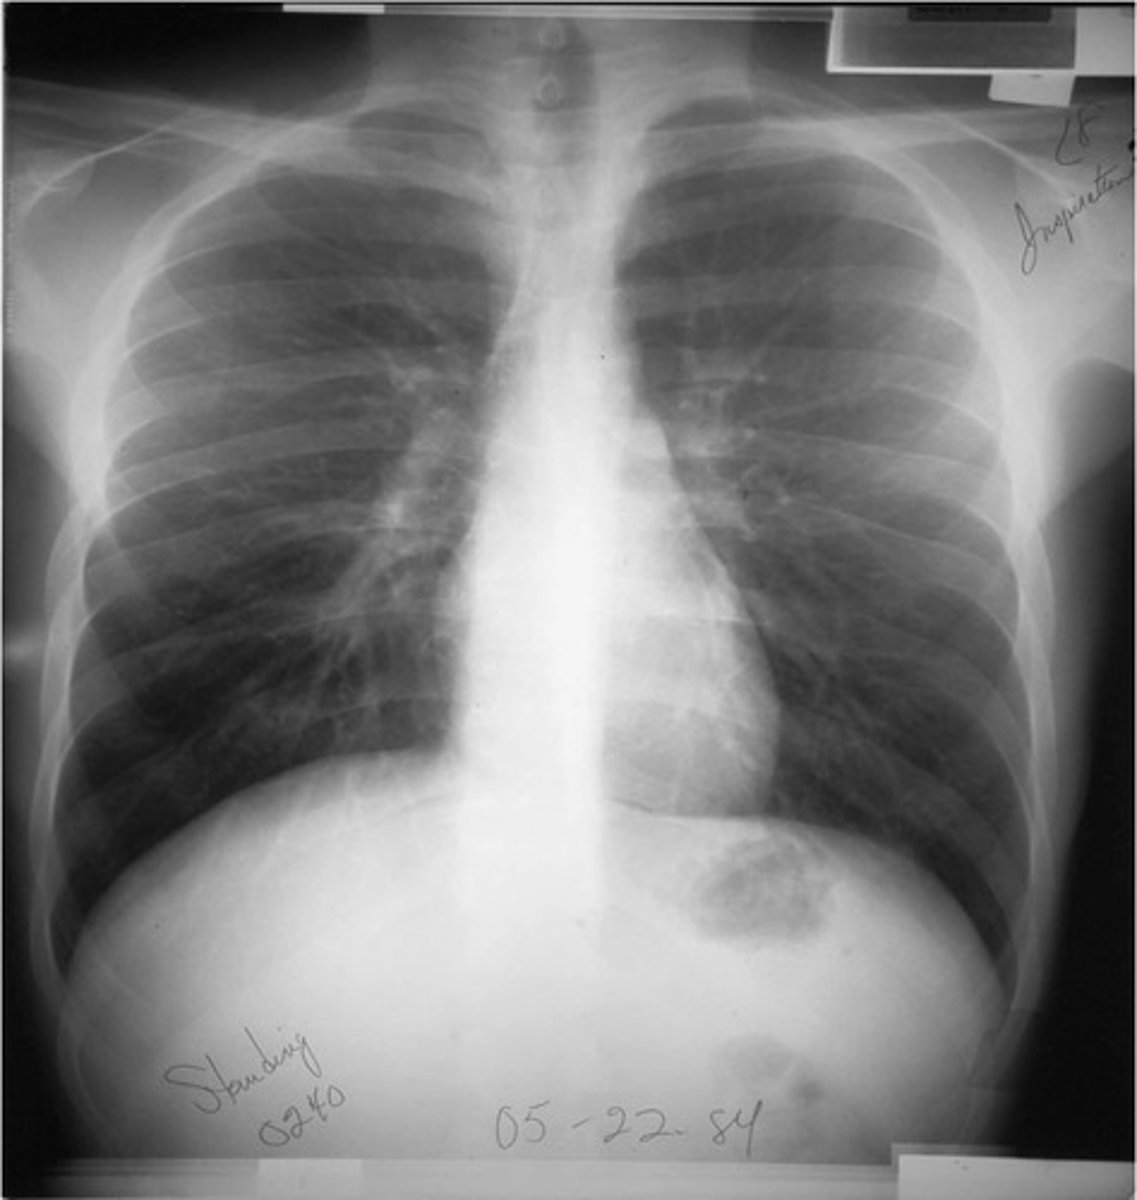

-posteroanterior view -goes from back to front

PA view